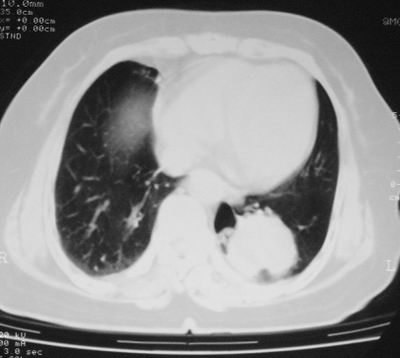

患者,女,64岁,4年前左腮腺"多形性"腺瘤手术治疗史.现复查胸部ct见左下肺块状影,该影与原左腮腺手术是否有联系?

本次复查胸部ct

左下肺软组织块影,有分叶、毛刺、空泡及胸膜牵拉征,左下肺周围性肺癌。

左肺下叶周围型肺癌,支持!(软组织肿块+分叶+毛刺+空泡+胸膜凹陷征)

左下肺软组织密度影,可见分叶,边缘可见毛刺征,胸膜增厚,强烈要求左下肺周围型肺癌

左下肺后基底段实性肿块,周围有毛刺,病变周围有肺气肿,与降主动脉间有条带状影相连,病灶4年前查体发现,纵隔内未见肿大淋巴结。考虑.肺隔离症,建议增强扫描与周围型肺癌鉴别。